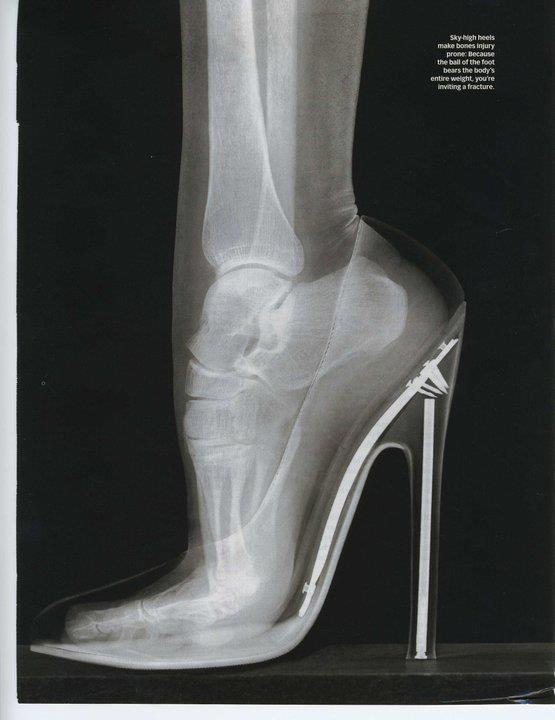

[흥미돋]하이힐 신은 발 엑스레이

• 작성자이성애강요를멈춰주세요 | 작성시간 23.05.06 현대판 전족 그 잡채

• 작성자아이텐팃티 | 작성시간 23.05.06 와 예전엔 나도 신고 다녓는데 지금보니까 전족보는 기분임 ㅋㅋㅋ